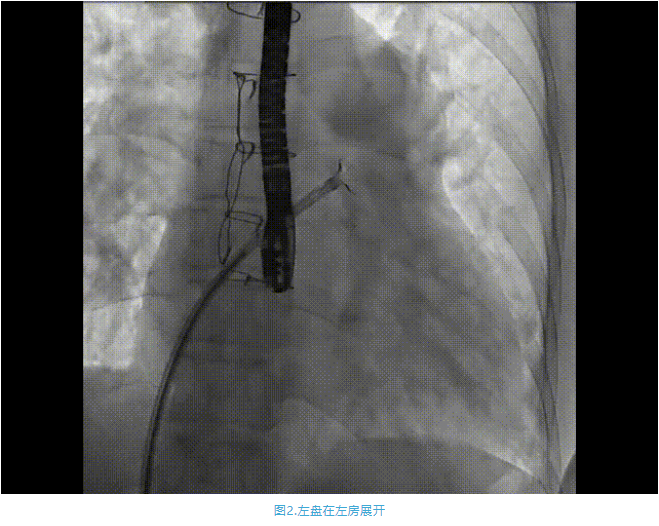

術中首先在局麻下穿刺股動脈、股靜脈,完成心導管檢查評估后轉為全麻,在食道超聲引導下穿刺房間隔,穿刺成功后將加硬導絲送入左上肺靜脈建立軌道,根據患者病情行球囊預擴張后植入6mm孔徑房間隔造孔支架,經透視及食道超聲評估支架左右盤展開良好,夾持于房間隔兩側,固定穩定、位置良好,食道彩超顯示房水平右向左為主分流,分流孔直徑符合預期大小,心導管檢查評估達到預期效果,釋放造孔支架。術后12h患者下床活動,恢復順利,擬于近日完善術后評估后出院。